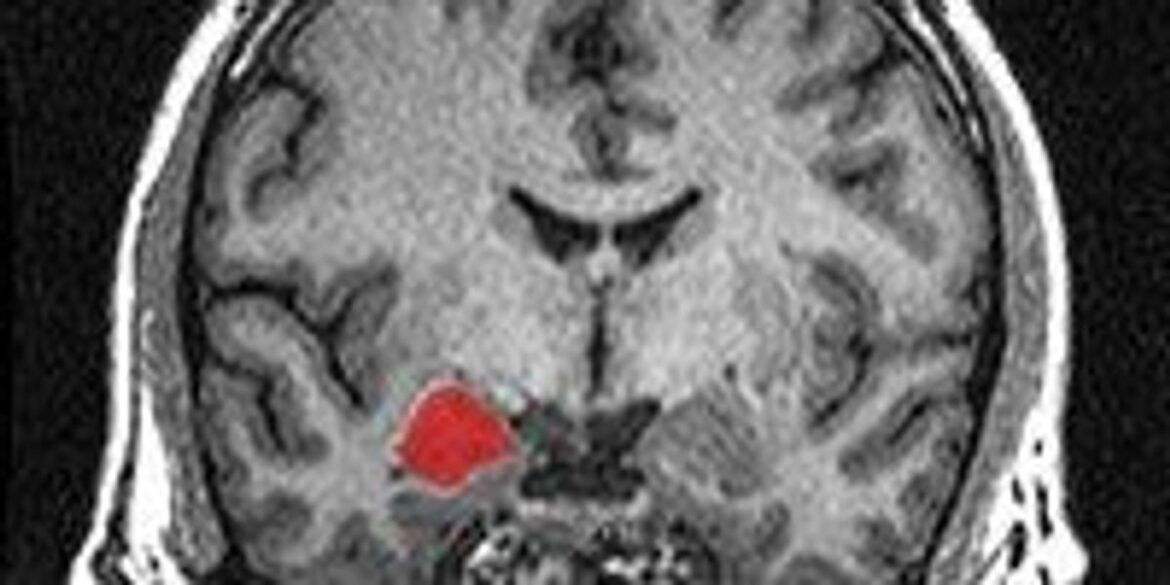

Los síntomas incluyen ronquera crónica, cicatrices cutáneas, bultos en los párpados y, en el aspecto neurológico, daños en la amígdala, la zona cerebral que regula emociones y percepción del peligro. Esto impide a los pacientes sentir miedo o reconocer expresiones faciales.